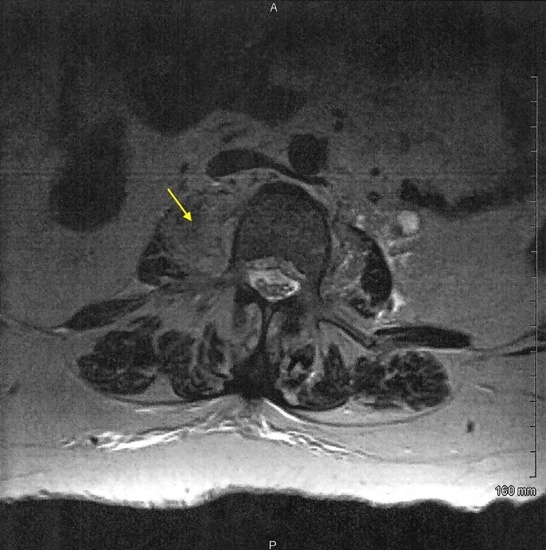

A lumbar spine MRI with and without IV contrast was obtained and revealed a low-density collection with peripheral heterogeneous and enhancement in the right psoas muscle measuring approximately 3cm by 1.5 cm extending to the right from the L2-L3 disk space (Figure 1). A subtle lucency along the inferior endplate of L2, suggestive of a developing fracture line, was also noted. The central canal of the L2-L3 space demonstrates moderate central canal stenosis. Also noted was an additional abscess more inferior to the original abscess. There was also a suggestion of septic synovitis of the posterior facets from L2 to L4 (Figure 2). Moderate hydro ureteral nephrosis was still present on the left. The left psoas muscle was normal.